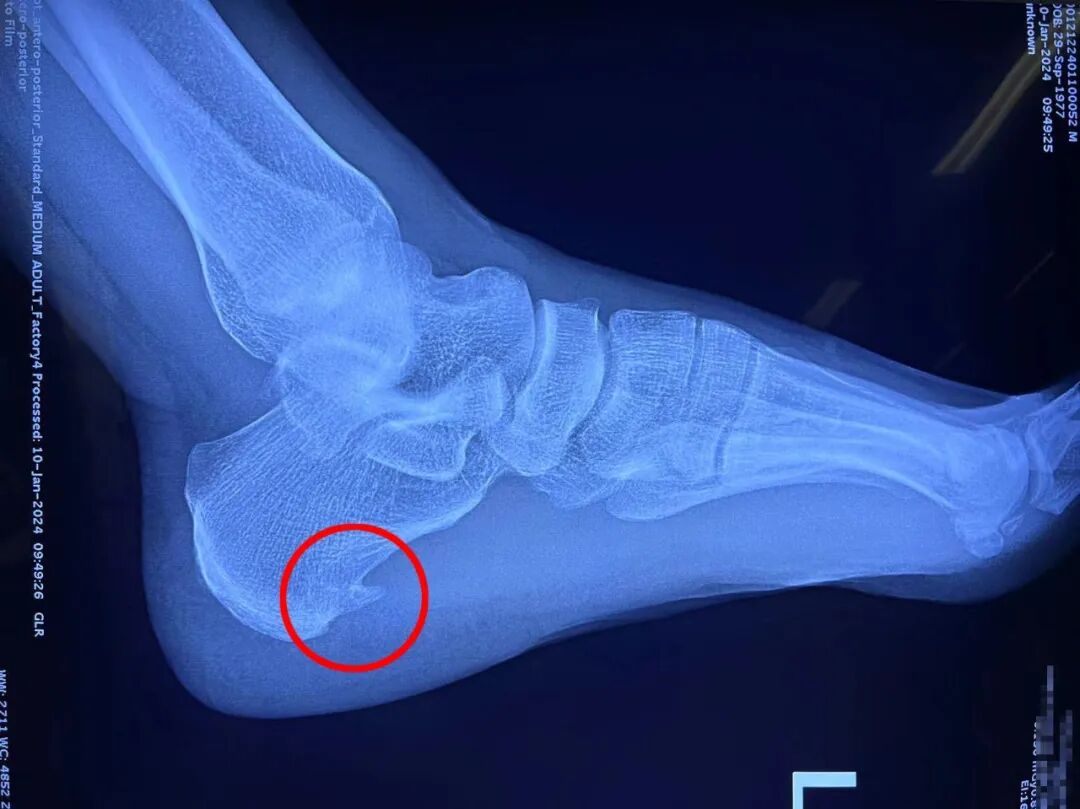

就在李大哥迷茫、纠结之际,偶然在网上看到了来自荆门市人民医院宣传视频——跟骨骨刺微创切除术。李大哥便立即联系发布视频的医生,几经辗转找到了该院关节外科的徐立副主任,起初通过电话问诊,但无法了解患者具体情况,徐立便提出微信好友申请,告知李大哥先在当地拍一张X片,以便了解具体位置、大小等。

▲李大哥脚后跟的“骨刺”

2024年1月15日李大哥办理了入院手续,完善相关检查无手术禁忌症后,徐立便组织进行术前讨论,向李大哥说明手术注意事项。两天后,在副主任徐立、副主任医师金涛及周峰的配合下进行了“关节镜下跟骨骨刺切除术+足底筋膜松解术”,术中无出血,仅用25分钟就完成了骨刺切除,术后拍片骨刺消失。手术当天,李大哥未感觉疼痛,伤口无渗血,麻药消散后责任护士便立即指导进行足趾活动。

▲术后“跟骨骨刺”消失